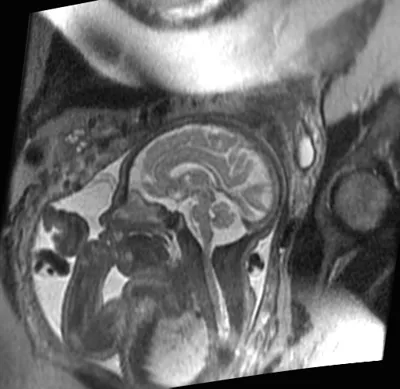

fetal mri baby scan

MRI image of a 30 week fetus shows normal fetal brain on this sagittal image (acquired in the midline of the brain). Notice how much detail can be seen of the foldings (sulci and gyro) of the brain, the brain stem, and the cerebellum.

UCSF is one of the few sites in the country that is experienced with performing and interpreting fetal MRI. We have performed fetal MRI since 1996. The findings from our fetal MRI study will help us provide pregnant women with the most advanced and accurate information during their pregnancy.

First, we would like to see how accurately fetal MRI detects changes in the fetus’ brain and spine during pregnancy compared to ultrasound.  While ultrasound is the most commonly used method of monitoring fetal development, its ability to detect changes in the brain is limited.  In this study, we are comparing ultrasound and MR images of fetuses to identify the situations in which fetal MRI will provide valuable clinical information not seen on ultrasound.  Studies have shown that, overall, fetal MRI is more helpful than ultrasound in evaluating the brain. We are interested in studying just how helpful fetal MRI is for different brain conditions.